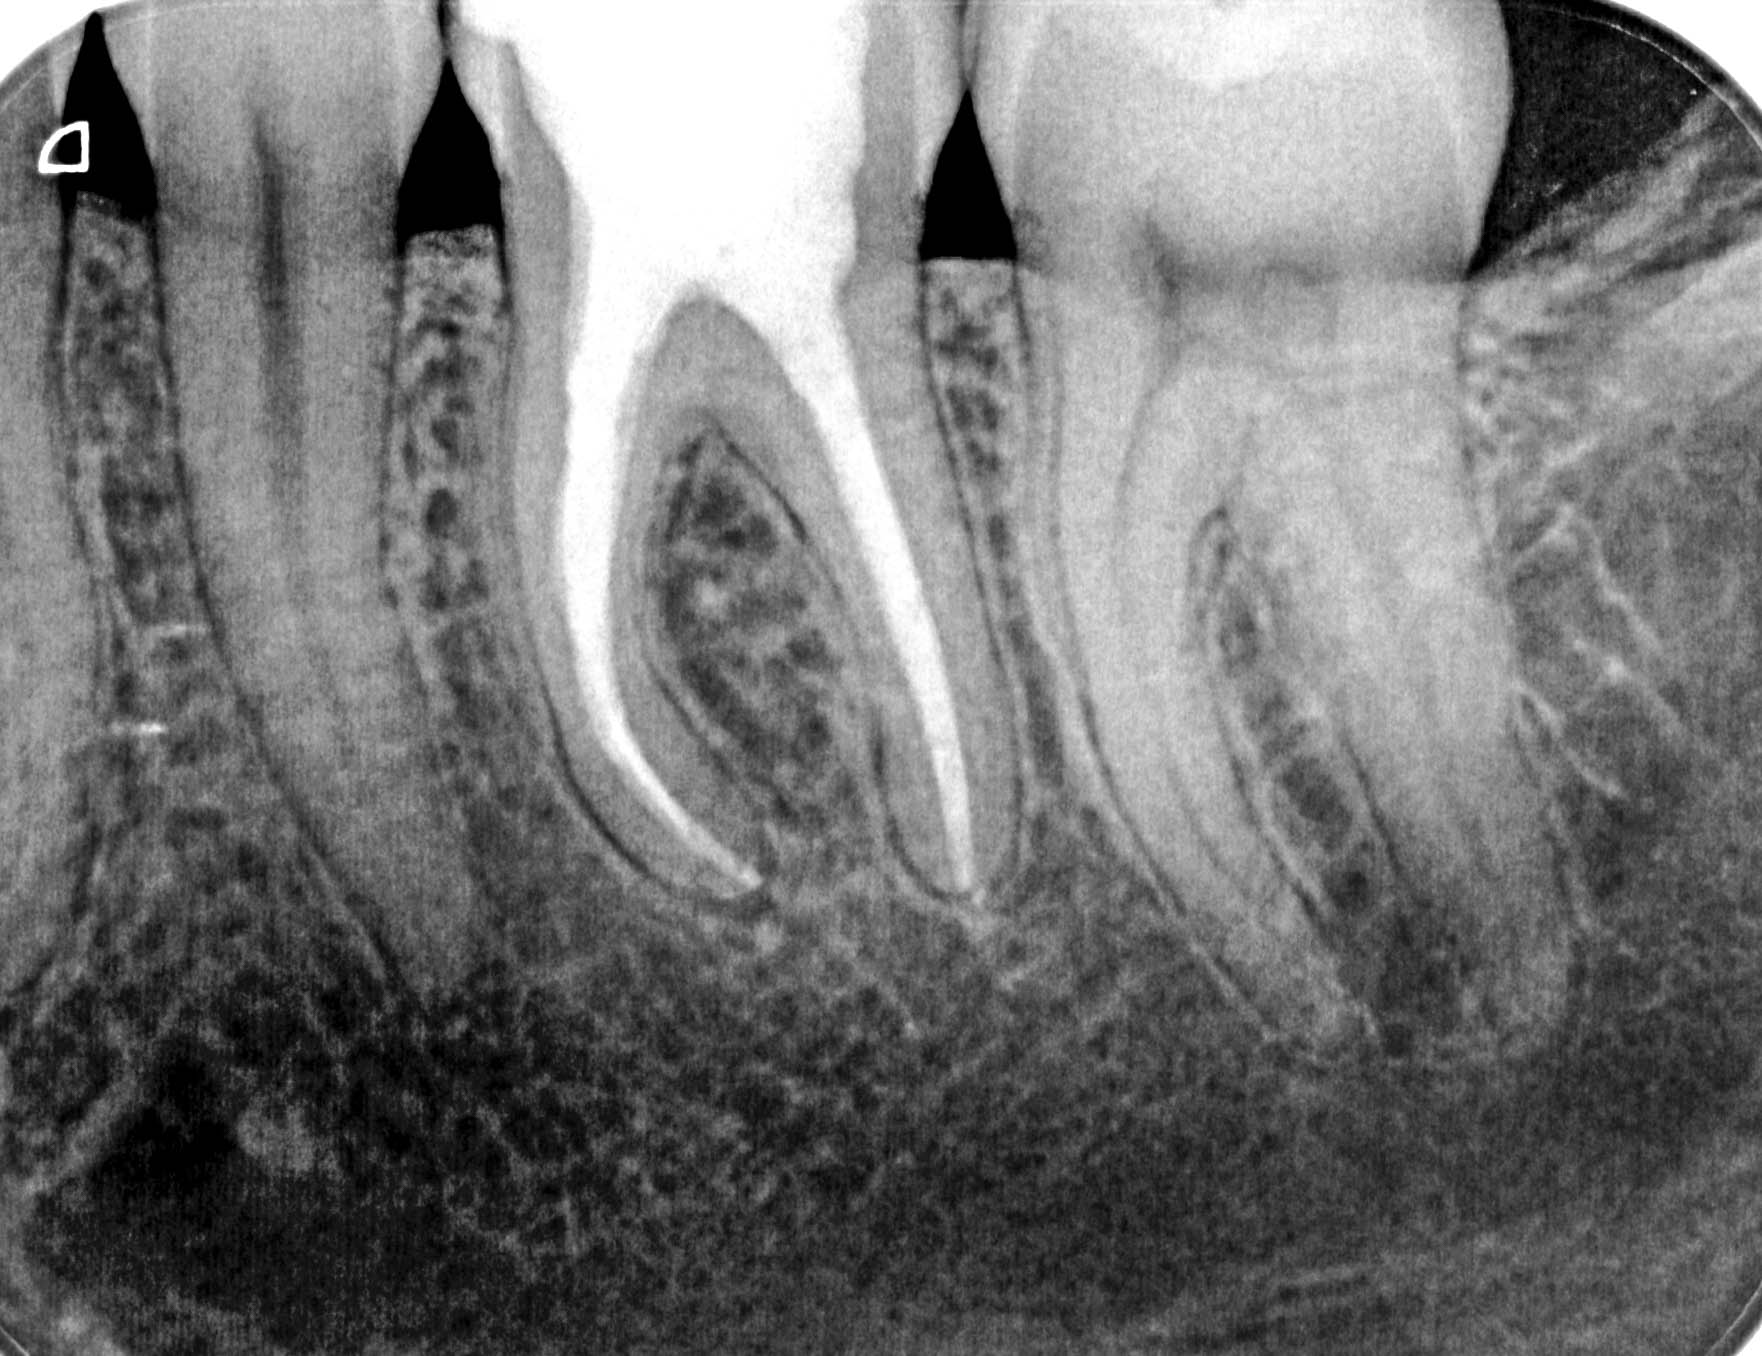

12.12.2013 Veröffentlicht 14. März 2016 am 1762 × 1356 in Calciumhydroxid – Überpressung (1) 12.12.2013